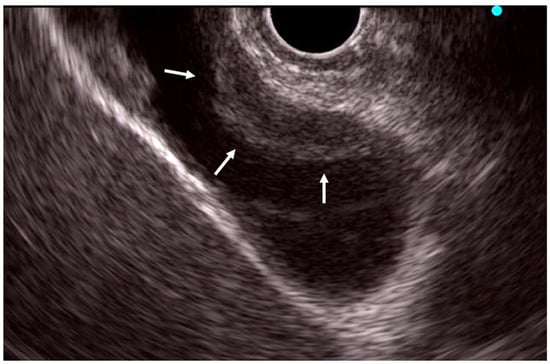

A characteristic ERP finding in AIP is distinctive narrowing of the MPD [48,49,50,51,52]. Diffuse-type AIP demonstrates narrowing along more than one-third of the MPD. Long-segment or multiple skipped narrowings are specific pancreatographic features of AIP, and ERP is unnecessary when these are evident via MRCP. However, focal narrowing (less than one-third of the MPD) may be evident in focal-type AIP. ERP is useful in such cases, particularly when histologic evidence of AIP or malignancy exclusion via EUS-TA cannot be obtained. Key ERP features of AIP include narrowing along more than one-third of the MPD, multiple skipped narrowings, absence of upstream MPD dilation (<5 mm), and side branches arising from narrowed segments (Figure 3). In contrast, PC typically presents as a short, single MPD stricture with upstream dilation. Long or multiple skipped narrowing of MPD without marked upstream dilatation are defined as level 1 ductal imaging criteria in the ICDC [15]. In JPS2018, ERP findings were considered equivalent to a combination of MRCP and negative cytologic findings for malignancy via EUS-FNA.

Figure 3.

Endoscopic retrograde pancreatography showing the skipped narrowing of main pancreatic duct in the pancreatic head and tail. Side branches arise from main pancreatic duct narrowing. Arrows: skipped narrowing of main pancreatic duct.